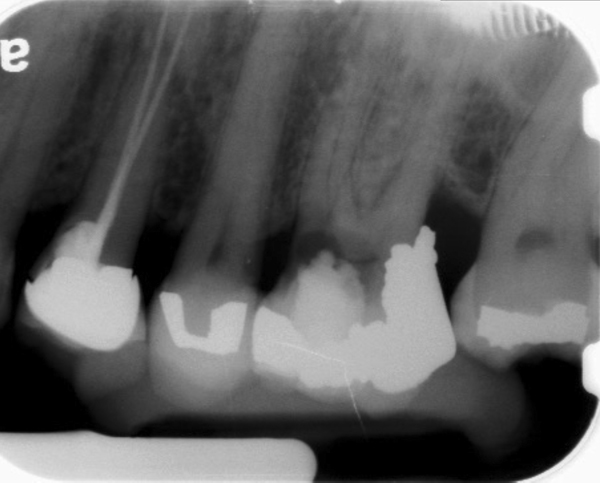

Fig 9 Preoperative radiographs showing mesial perforation.

Figure 9

Fig 10. Preoperative radiographs showing mesial perforation.

Figure 10

Clinical procedure: Once a perforation occurs, the extent of the perforation must be assessed. If there is an adjacent bony defect, the bony defect should first be filled with an osteoconductive or osteoinductive material. This can be done with a bone graft, calcium sulfate, or collagen/gelatin sponge. The dentinal portion of the tooth that has been perforated is then restored with MTA (Figure 9 through Figure 14).